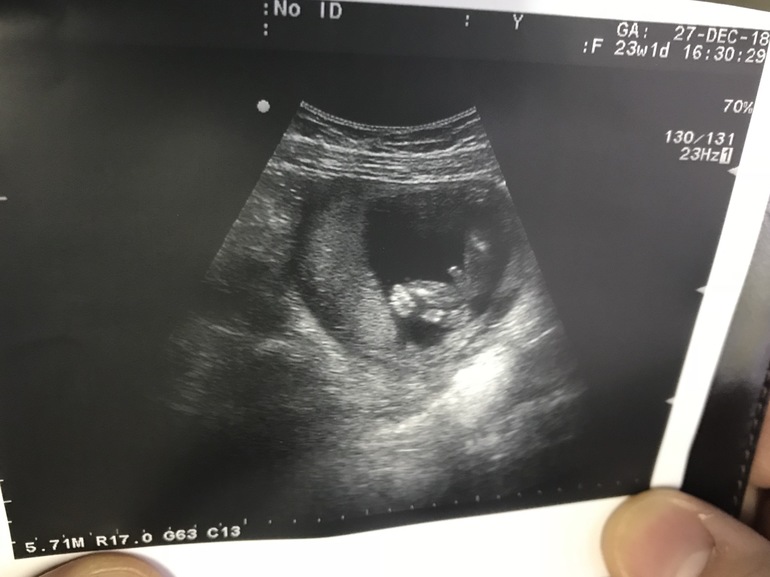

А у меня на довольно приличном сроке УЗИстка с опытом нашла пипку у дочки😀и не верить ей оснований не было, многим знакомым она правдиво сыновей увидела😀да ладно моя мама решила, что покупать будет и тот и тот цвет приданого, а то я выбирала то всё на пацана. И пришлось бы нашей Евгеше во всем мальчиковом быть😀😀😀

Ну я вот реально не понимаю, так как мне и самой без опыта всё видно, а у дочки на втором скрининг помню очень ответственный казистый попался, что прям показывал нам где там левая, а где правая подовая губа🤣🙈🙈 так что я реально не понимаю, как можно ошибиться🙈 ещё на раннем сроке да, но недель с 16 уж всё видно, а на втором кометное так вообще отчетливо😁😁

Когда родила, мама моя шутила, что доча моя просто ручку вниз опустила и фигу показывала УЗИстке, вот она за пипку и приняла😀 Но вот родила недоношенную, и у нее та спорная часть тела хоть и была не сформирована до конца, но блин, там вообще сходства с мальчиковым не было. Тоже в недоумении, как можно принять девчонку за мальчишку))

Оборудование не особо хорошее в нашей ЖК, монитор маленький и не вертится, по крайней мере так говорила УЗИстка, мне в нашей ЖК никогда ляльку не показывали, только на скринингах

О да, у нас в ЖК тоже доисторический аппарат🙈🙈 не удивительно, что они не таком так часто ошибаются. Я по/этому туда не хожу, как-то нет доверия к такому аппарату🙈